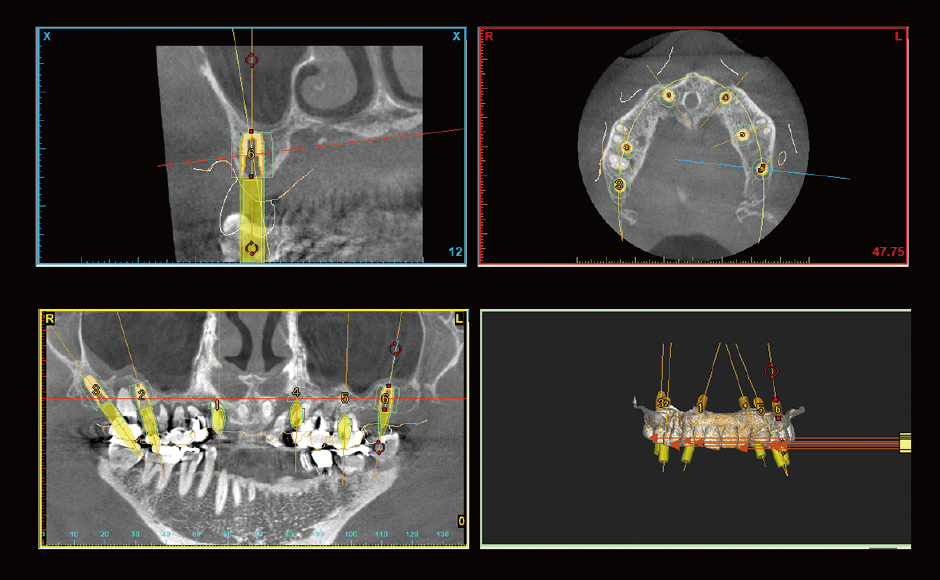

症例3:上顎残存歯を全て抜歯し、オールオン6による即時荷重